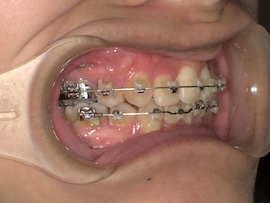

前回から1ヶ月後の歯並びはこんな感じです。

左上親知らずの牽引を始めてたった1ヶ月ですが、かなり出てきている気がします。